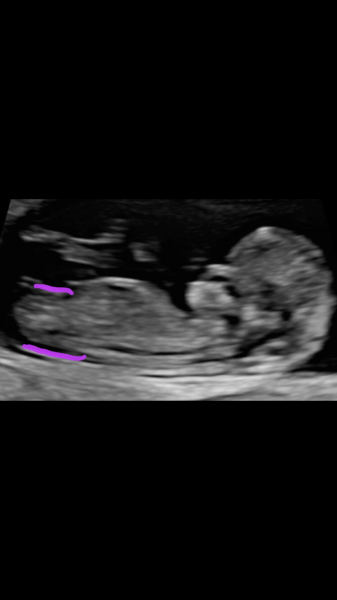

@Janefx40 here's an 11 week scan and 12+6 if you fancy a guess!

@IWillBeWaxingAnOwl your baby is cute! Obviously I really have no idea but my guess is a girl. I'm assuming that white line is the nub but really it could be anything